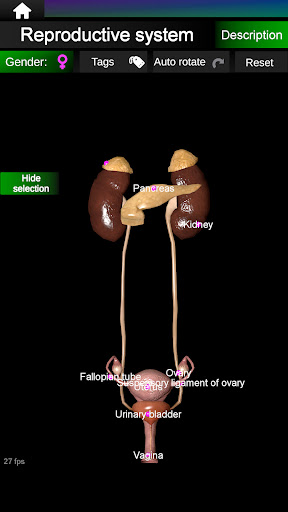

* Reproductive system, which includes the male and female reproductive organs.

Shows a 3D anatomical model of the main organs of the human body and a description of each one.

* Easy to access and navigate (zoom, 3D rotation).

* Hide or show information.

* Compare male and female organs.

* Descriptions of each organ.